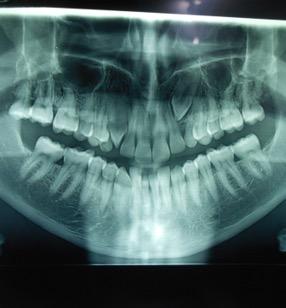

Στην ηλικία των 7 ετών, σύμφωνα με τις οδηγίες της Αμερικανικής Ορθοδοντικής Εταιρείας AAO (American Association of Orthodontics), καλόν θα είναι να εξετάζεται κλινικά αλλά και ακτινογραφικά η κατάσταση της μεικτής οδοντοφυίας του παιδιού για σκελετική ή οδοντική ασυμμετρία των γνάθων, για ελλείποντα δόντια ή δυνητικώς έγκλειστα ή για παρουσία οδοντωμάτων ή για έκτοπη ανατολή

Γενετικώς ελλείποντα δόντια (ο άνω αριστερός πλάγιος, ο άνω δεξιός 2ος προγόμφιος, οι κάτω δεύτεροι προγόμφιοι αμφοτερόπλευρα.)

Μετά το πέρας της ορθοδοντικής θεραπείας, (2η φωτογραφία), τα κενά που δημιουργήθηκαν

από την έλλειψη των μονίμων δοντιών μετά την φυσιολογική απόπτωση των νεογιλών δοντιών, έκλεισαν με ορθοδοντική παρέμβαση